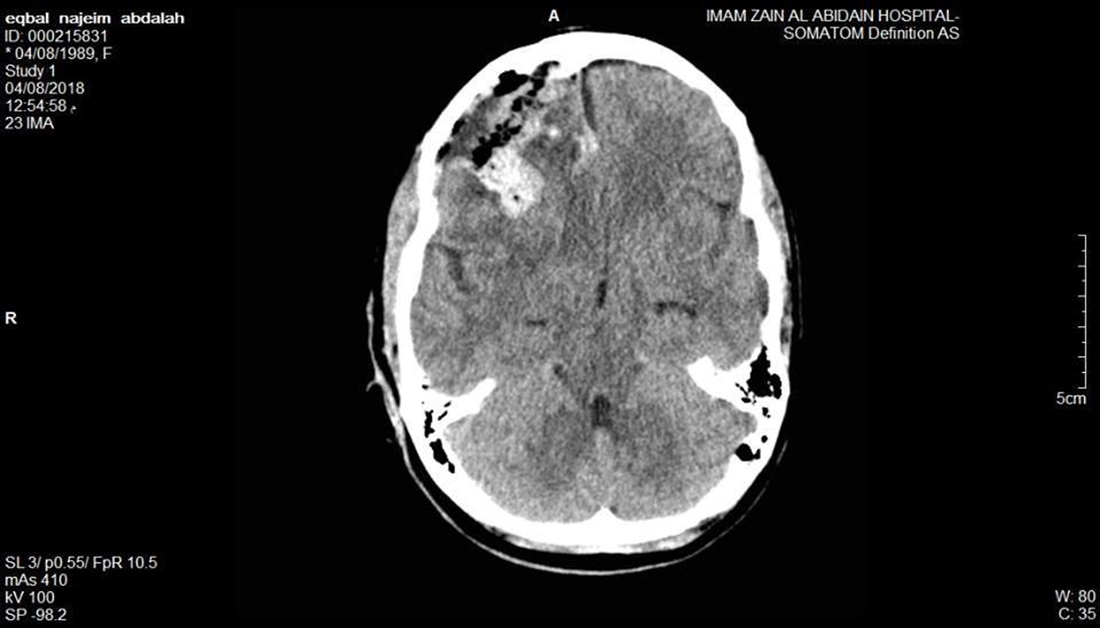

اعلنت مستشفى الامام زين العابدين عليه السلام التابع للعتبة للحسينية المقدسة عن نجاح فريقها الطبي باستئصال ورم في الدماغ لمريضة عشرينية.

وأفاد اعلام المستشفى,لوكالة نون الخبرية  انه بعد اجراء الفحوصات الطبية والرنين المغناطيسي للمريضة تبين انها مصابة بورم جبهي ايمن في الدماغ.

وأضاف , اجريت للمريضة عملية جراحية وتم خلالها استئصال الورم الدماغي مجهريا.

وأشار الى ان المريضة الان بحالة صحية جيدة وفي تحسن مستمر.